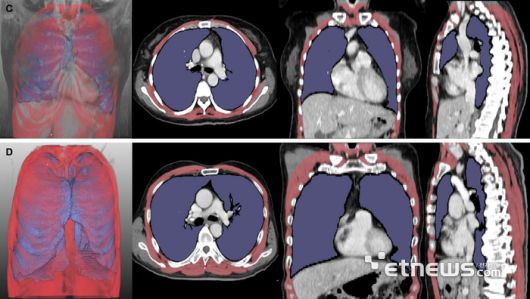

루게릭병 환자의 흉부 CT 분석 결과. 폐 용적 지수(LVI, 보라색)와 호흡근 용적 지수(RMI, 빨간색)가 낮은 환자는 높은 환자보다 생존 기간(위 5개월 vs 아래 43개월)이 짧았다. |

연구팀은 이러한 문제를 해결하고자 딥러닝 소프트웨어를 활용해 흉부 CT 영상에서 폐와 호흡근 부피를 수치로 산출(LVI, RMI)하고 이를 분석했다. 루게릭병 환자 261명의 흉부 CT를 분석해 진행됐으며, 폐·호흡근 용적 지수가 병기가 진행될수록 유의미하게 감소하는 것이 확인됐다. 이 지수들이 낮은 환자군은 기관절개술을 받거나 사망에 이르는 시점이 빠른 경향을 보였다.